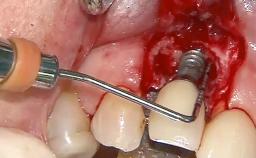

Despite anti-infective surgical treatment, some patients may experience recurrent infection and progressive bone loss requiring additional treatment. Removal of Implant Due to Recurrent Infection describes a conservative approach using an implant retrieval tool without the need for excessive bone removal or use of a trephine.